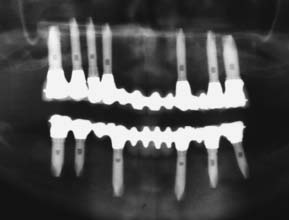

For completely edentulous patients who require nonremovable restorations, there are two implant options: a complete metal-resin fixed dental prosthesis and a metal-ceramic fixed dental prosthesis (Figs. 13-48 to 13-50).

Fig. 13-48 A to D, A metal-ceramic implant restoration may be indicated if adequate bone and soft tissue contours are available.

Fig. 13-49 Radiograph showing fixed restorations supported by seven implants in the maxilla and six in the mandible. Radiograph of patient in Fig. 13-48.

The complete metal-resin fixed dental prosthesis is a cast alloy framework with processed denture resin and teeth. It is typically supported by a minimum of five implants in the mandible and six in the maxilla. One major determining factor for selecting this option is the amount of bone and soft tissue that has been lost. For patients who have had moderate bone loss, the prosthesis restores both bone and soft tissue contours.

The metal-ceramic prosthesis also requires a minimum of five implants in the mandible and six in the maxilla. It can be made esthetically pleasing only if bone loss is minimal and is best suited for patients who have recently (within 5 years) lost their natural teeth. For patients with severe bone loss, there is probably only one option: a removable restoration (Fig. 13-51).

The main advantage of a fixed restoration, whether it is metal-resin or metal-ceramic, is that it is attached to the implants at all times. Therefore, patients experience the psychologic benefit of having a restoration that closely resembles their original natural teeth. In addition, movement within the system is minimized, and the components tend to wear out less quickly. Because the prosthesis is screw retained, the dentist can remove it, allowing access for cleaning and repairs. A potential disadvantage is that the implants must be precisely placed, especially in the maxillary anterior esthetic zone. Implants placed in embrasure spaces can lead to disastrous esthetic results and can impede access for hygiene. With a metal-resin prosthesis, the clinician must decide between leaving enough space for hygiene access and minimizing space for optimum esthetics. Some patients may be concerned by the amount of metal shown in a metal-resin prosthesis. However, from a conversational distance, a properly made prosthesis is hardly noticeable. Esthetic and phonetic problems in the maxillary arch can often be avoided by not placing implants near the midline and restoring the incisor teeth with pontics. This approach to implant placement improves the restorative outcome considerably (Fig. 13-52).